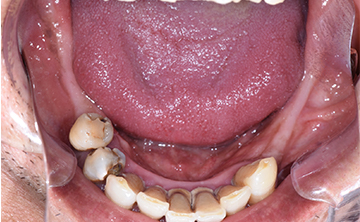

虫歯を放置して10年くらいの症例です。お口の中には、上あごは、一本しか歯が残っておらず、全く噛めないということで来院された患者さんです。痛い時期はどのようにして過ごされたのかと聞くと、とにかく痛み止めとお酒で痛みをごまかして過ごされたそうです。

すごい良く我慢されましたねとお伝えして、今後は、痛い時は安心してご来院くださいと伝えたら、ホッとされていました。小さい頃のトラウマで、とにかく歯科医院に行くことが怖かったそうです。

10年間虫歯を放置すると虫歯というより、歯が無くて噛めないので、咀嚼という問題が発生します。食べ物をお口の中へ入れても噛めないので、そのまま丸のみという食事になってしまうと胃や腸への負担は必須となり、癌や他の疾患へかかりやすますね。